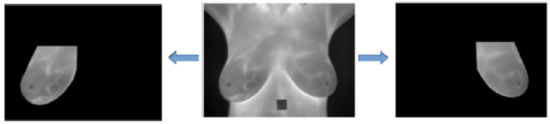

The DIT thermal images contain areas of the patient’s skin that are not important in the context of the addressed problem: only the breasts are considered to be the Region of Interest (ROI). The segmentation of the ROI for a given patient can be seen in Figure 4.

All 1280 images (64 breasts, each with 20 sequential images) used in the learning stage of the method and the 240 images (12 breasts, each with 20 sequential images) used in the test step were manually segmented using the GIMP tool [18], which is a free image editing software. During this process, three people were responsible for these segmentations. Two of them were responsible for manual segmentation, while the third checked whether segmentation was done properly. If it was not proper, segmentation was repeated. All segmented images are available at http://visual.ic.uff.br/proeng/thiagoelias/.

Figure 4. Result of the Region of Interest (ROI) segmentation. Copyright © 2019 IEEE, all rights reserved.